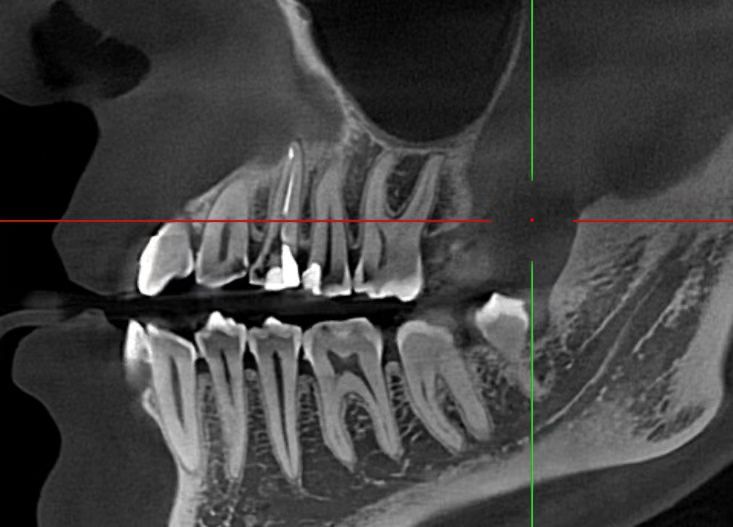

Radiographic evaluation confirmed inadequate previous obturation and a separated instrument fragment visible in the apical third of the buccal canal.

Access cavity refinement was performed under high magnification with a dental operating microscope to ensure optimal visibility and precision. The separated 2 mm instrument fragment was identified in the apical third of the buccal canal.

An ultrasonic E6 tip was applied with gentle, controlled vibration to conservatively trough dentin around the fragment and loosen it without excessive removal of tooth structure. Continuous microscopic monitoring allowed safe, atraumatic retrieval of the fragment without perforation or significant dentin loss. Magnification proved essential for preserving root integrity during this critical step.